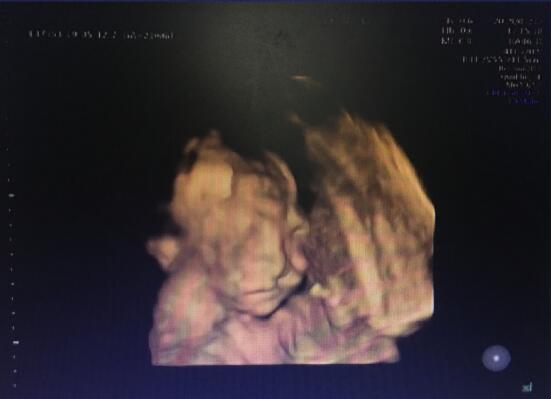

5月12日,正值母親節(jié),本是象征著愛意和美好的一天,但孕21周的二胎孕媽黃女士在武漢仁愛醫(yī)院做四維大排畸檢查時卻收到了一個晴天霹靂。

“胎兒嘴唇上有裂縫,為唇裂。”武漢仁愛醫(yī)院超聲影像科王娟主任說道。

得知檢查結(jié)果,黃女士一家都很震驚,本來懷二胎是全家都很開心的事情,沒想到卻被診斷胎兒有問題。“武漢仁愛醫(yī)院醫(yī)生告訴我檢查結(jié)果時,我的第一反應(yīng)就是弄錯了,前不久我才在當?shù)蒯t(yī)院檢查了并沒有問題,這怎么就出現(xiàn)了唇裂呢?”

明明之前才在當?shù)蒯t(yī)院做了檢查胎兒都還是正常的,不同醫(yī)院產(chǎn)檢,為什么結(jié)果卻截然不同呢?針對孕婦的疑問,王娟主任解釋道:“根據(jù)胎兒發(fā)育情況,每個階段檢查胎兒的側(cè)重點不一樣,另外不同時間不同儀器檢查結(jié)果會有誤差,不存在做完哪些項檢查沒問題,就一定能確定胎兒以后是安全健康的,孕婦按時產(chǎn)檢是相當有必要的。”

武漢仁愛醫(yī)院超聲影像科王娟主任正在為孕婦做檢查

武漢仁愛醫(yī)院王娟主任在此提醒大家:“孕期該做的篩查都要做,個人的健康狀況和家庭遺傳對于寶寶的健康影響只是很小的一部分,寶寶的畸形是由很多方面的因素引起的,不容忽視。同時孕婦一定要到專業(yè)的醫(yī)院進行產(chǎn)檢,因其有先進的儀器、規(guī)范的流程管理、經(jīng)驗豐富的醫(yī)師,生命不允許不專業(yè)更不允許失誤。